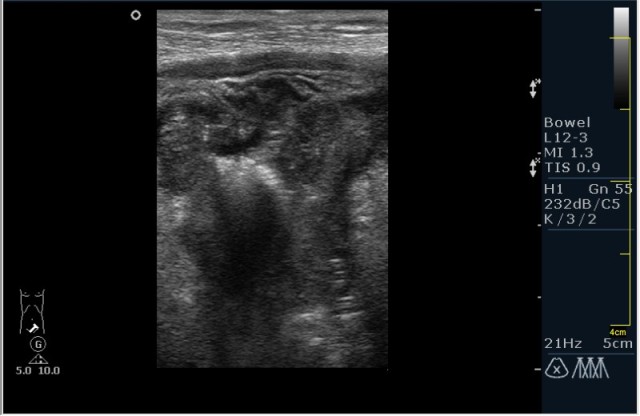

Пациент М. 60 лет с болями в левой подвздошной области. Пациент был направлен на УЗИ с диагнозом: левосторонняя почечная колика. Жалобы на боли в левой подвздошной области отдающие в таз. Анамнез без особонностей.

Пациента я сразу направил на эндоскопию. К сожалению, заключение было ожидаемым с моей стороны, опухоль (карцинома по результату биопсии).